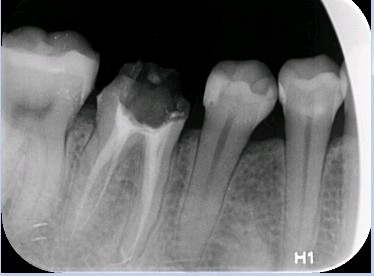

术中拆冠后

图片发自160App

进行 46 牙 纤维桩植入,45 牙旧充填物去除